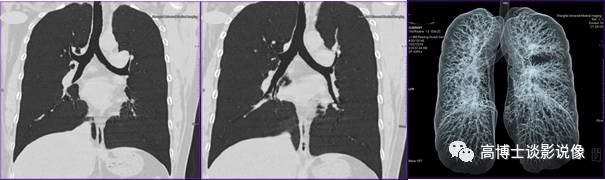

三、肺气道重建

双侧斜冠状位MinP(最小密度投影)显示气道情况。使用VRT虚拟成像整体显示气道情况(密实或透明化)。了解气道有无狭窄以及狭窄的位置、程度、范围、原因等,能无创性评价气道的狭窄,尤其适用于支气管纤维镜不能通过者;了解气道的顺应性等功能情况及气道狭窄周围肺组织的情况;气道狭窄支架置入术后,了解支架的通畅情况。